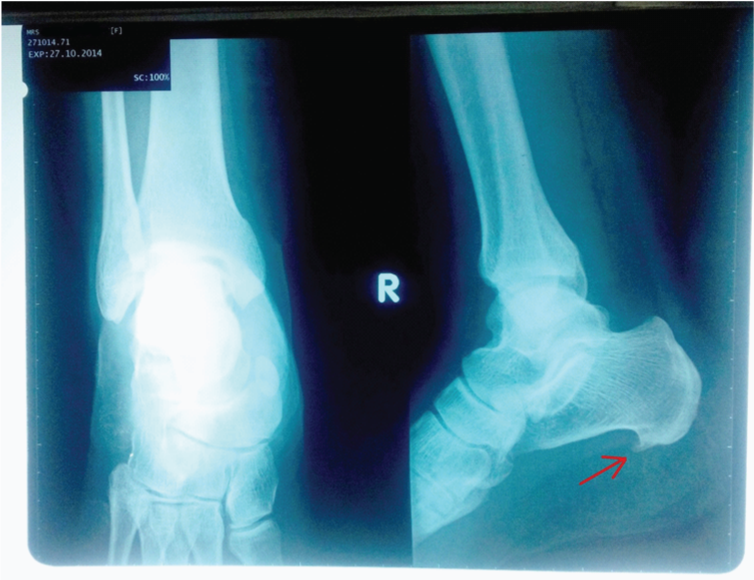

Mrs. SM who is a 44 year old female housewife visited Rotary Physical Therapy and Rehabilitation Center with complaint of severe heel pain in right foot. The pain started a year ago and was gradual and burning type. Her pain was worst in the morning and at the end of the day. However, it ceased after some movement. Moreover, her symptoms returned following prolonged standing and getting up from seated position or prolonged rest. She had history of high heel use at social gatherings and was very social. She carried out chores involving 4 hours of continuous standing and had an average 6-7 hours of standing a day. Furthermore, her height was 5 feet 1 inch and weight was 74 kilogram yielding a BMI of 30.2 kg/m2 and had no co-morbidities. Her pain was 7 on visual analogue scale (VAS) at the time of presentation. Tinnel sign for tarsal tunnel syndrome and squeeze test for calcaneal stress fracture were performed and results were negative. There was swelling and tenderness noticed at the heel and her Achilles tendon demonstrated tightness. Her X-ray showed a heel spur (Figure 1). Her treatment program included ultrasound at 1.5 watts/cm2 for 4 minutes, icing, gentle stretches to Achilles tendon for 10 times, intrinsic muscle strengthening and home exercises. Home exercises included myofascial release with tennis ball and tin, standing stretches to triceps surae and strengthening of intrinsic foot muscles on towel. After 2 weeks, she reported no significant improvement and her treatment plan were modified. After reviewing the literature, there was addition of iontophoresis with acetic acid, taping, stretching of the plantar fascia, and manual therapy of myofascial chains and use of heel pads. Emphasis was placed on manual therapy involving myofascial release and friction massage. Icing was replaced with heating modality. After 2 weeks, she had much improvement and her pain intensity was 3 on VAS. She was advised to take vitamin C (1-3 g/day) and glucosamine sulphate (500mg for thrice/day). Same treatment was continued for 2 more weeks and the patient was assessed for complaint of pain, the VAS score at this stage was 0. Duration of each treatment session lasted for 40 minutes. Patient was educated for preventing the recurrence of the problem and was emphasized to continue home exercises for further 2 weeks.

Figure 1 X-ray of the patient showing heel spur.